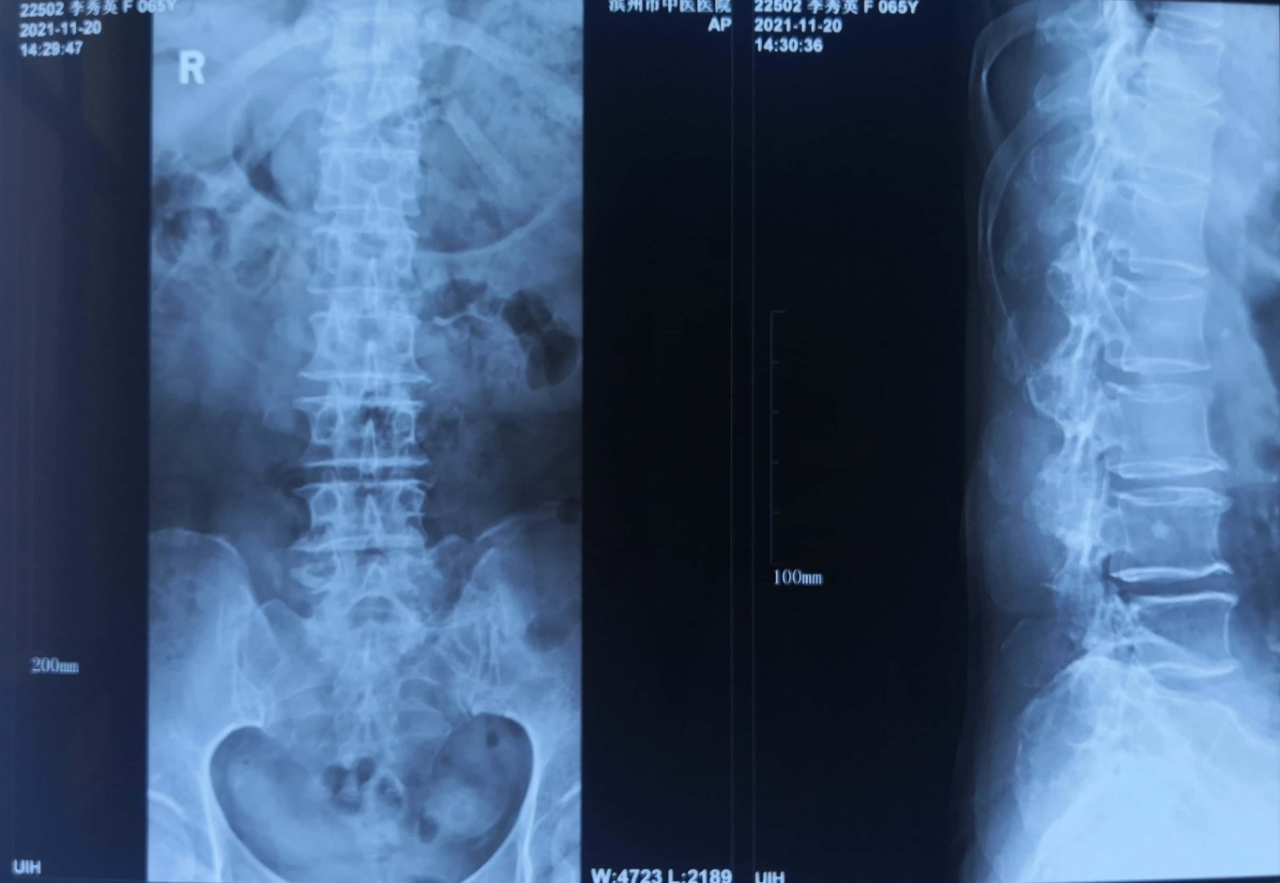

患者李某,女性,65岁。

主诉:腰部疼痛20余年,加重伴右下肢无力3年。间歇性跛行,跛距大约100米。

查体:腰椎生理曲度改变,L3/4/5棘突间及双侧压痛明显,叩击痛(+),无明显放射痛。屈颈试验(+),仰卧挺腹试验(+),直腿抬高试验右50°(+)左70°(-),股神经牵拉试验左(-)右(-),“4”字试验左(-)右(-)。右下肢肌力稍减弱,皮肤感觉正常,双侧膝腱反射(++),双侧跟腱反射(++),双侧BabinskiSign(-)。

诊断:1.腰椎椎管狭窄(L3/4) 2.腰椎滑脱(L3 I°)。